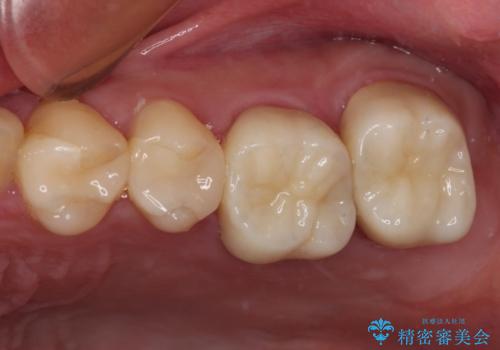

上顎犬歯や下顎大臼歯は、必要なところはインプラントを埋入することとしました。

クラウンが不適合であったり、根管治療の必要なほどの痛みのある歯であったり、見た目の気になる前歯などをオールセラミッククラウンに補綴治療を行うこととしました。